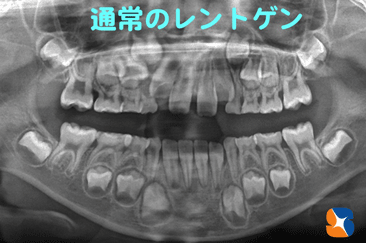

通常のレントゲンで歯並びを正しく予測するのは難しい

コラム「通常のレントゲンで歯並びを正しく予測するのは難しい」の画像